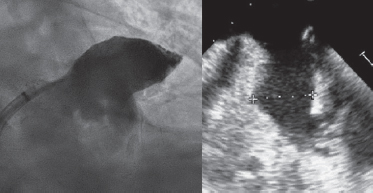

An 80-year-old male with permanent atrial fibrillation (informed consent obtained) underwent a percutaneous procedure to close the left atrial appendage (LAA). He had required repeated admissions for severe anemia and chronic gastrointestinal bleedings while on different antithrombotic regimens (aspirin alone, clopidogrel alone, apixaban). He had a CHADS-VASC2 score of 6 and a HAS-BLED score of 4. A transesophageal echocardiography (TEE) performed revealed the presence of Windsock morphology and no thrombus in the LAA. The diameters of the landing zone were between 23 mm and 25 mm (figure 1).

Figure 1.